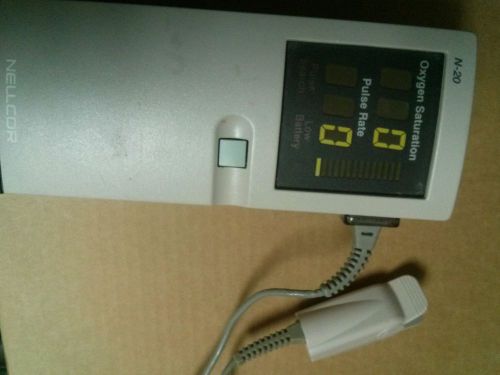

Nellcor N-20 with DS-100A Sensor